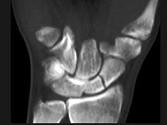

- 单项选择题男,21岁, 手部不慎摔伤,局部疼痛, 结合图像,最可能的诊断是 ( )

A、大多角骨骨折

B、小多角骨骨折

C、三角骨骨折

D、月骨骨折

E、舟状骨骨折